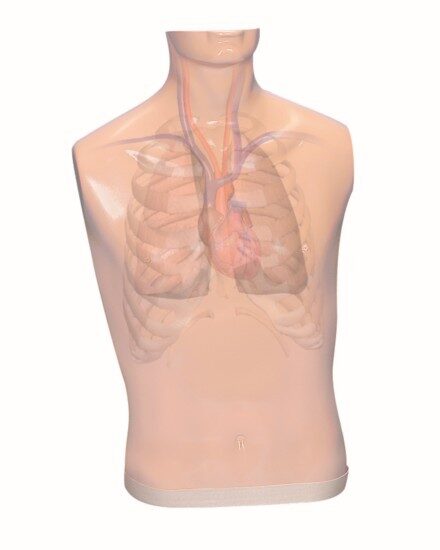

Simulaids Ausculation Trainer

Ausculation Trainer, Practice Board and Smartscope™

Ausculation Trainer, Practice Board and Smartscope™